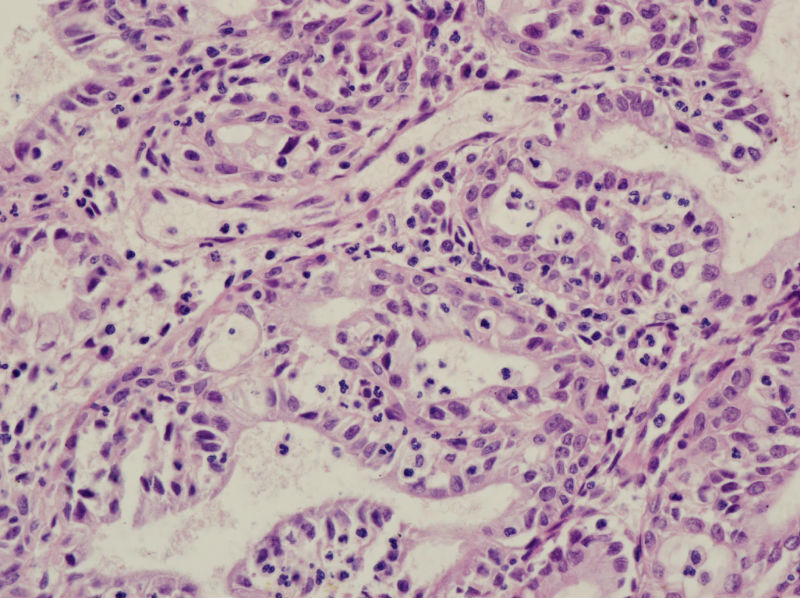

45岁,宫颈息肉?请老师指教

• 45岁,宫颈息肉?请老师指教图1

图1

慢性炎,腺体有鳞化

宫颈及宫颈内膜息肉,腺体增生及鳞化,鳞化跟中药没有关系,跟炎症刺激有关系。

宫颈息肉伴腺体鳞化,微腺体增生

宫颈息肉,伴有微小腺体增生。

宫颈息肉伴腺体的鳞化,我个人感觉息肉的分型比较复杂,有的地方存在宫颈腺体增生型,有些地方血管型,还有纤维型也可见。

宫颈息肉伴鳞化和微腺体增生

宫颈息肉伴糜烂,局部腺体及黏膜上皮鳞状上皮化生。至于说具体分型,与临床治疗和预后都没有关系,可以不分。

Benign endocervical polyp with SM and MGH. You do not need classify benign endocervical polyp because it has no impact on clinical management.